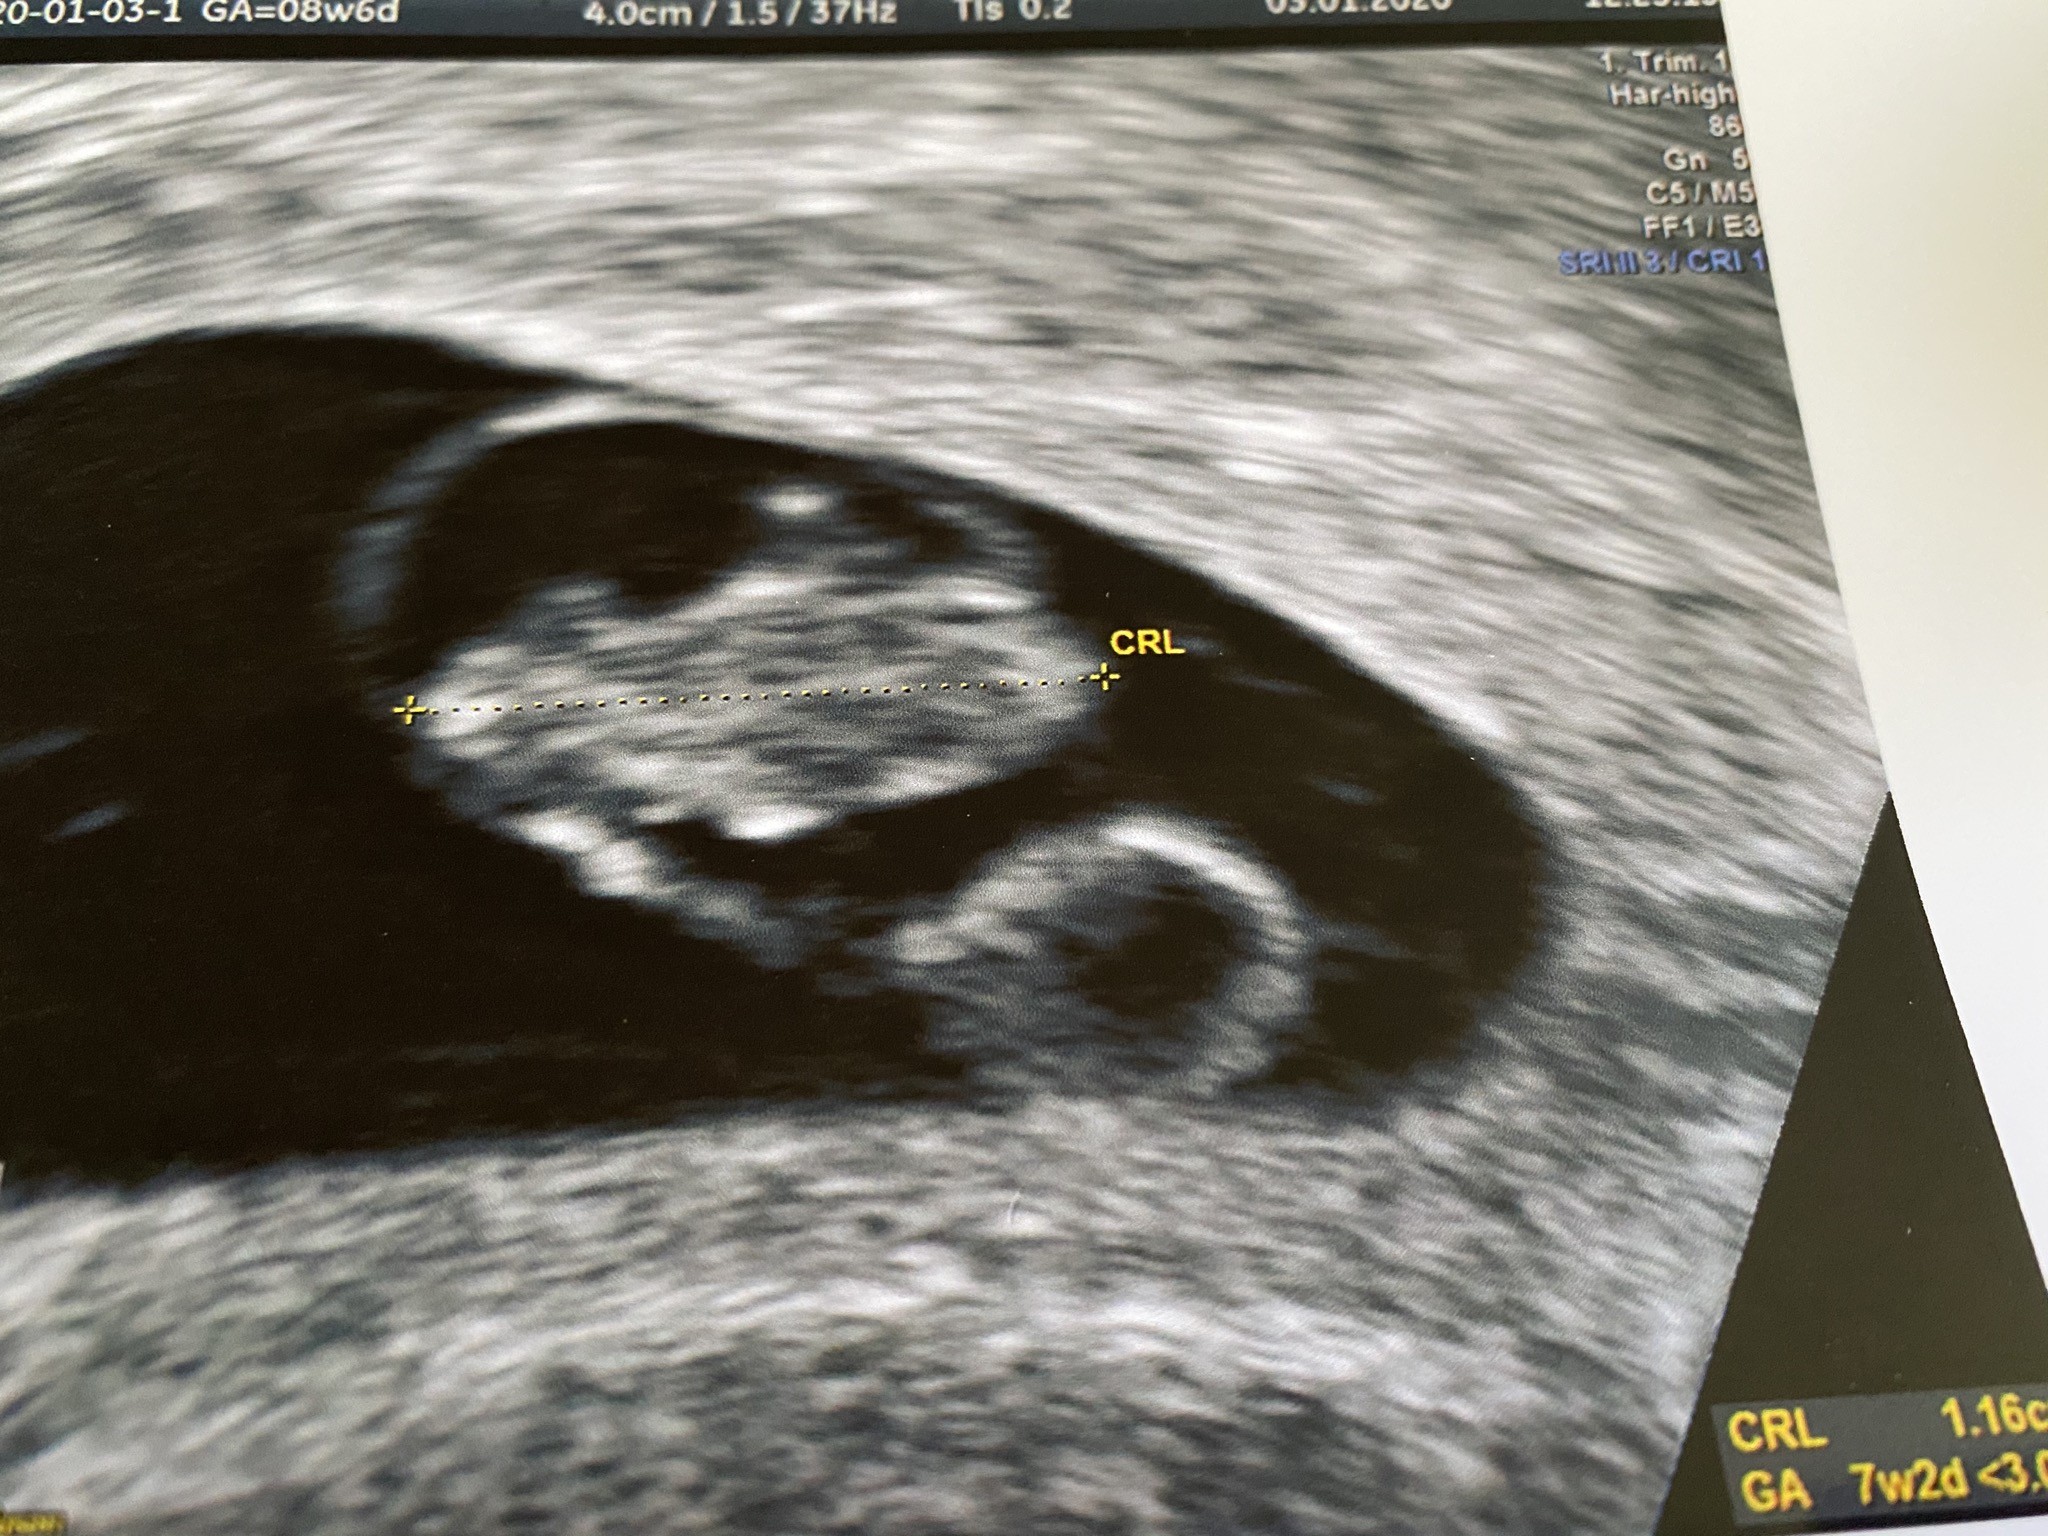

Została mi tylko pamiątka...

Załączniki

• 83FDAEC0-A626-46EA-9AAF-9C1F28CC2E61.jpeg

83FDAEC0-A626-46EA-9AAF-9C1F28CC2E61.jpeg

709,6 KB · Wyświetleń: 148

Matko patrzę na to zdjęcie i nie wierzę, mam nadzieję, że za kilka dni powiesz, że ktoś się pomylił. Wierzę w cuda serio, moja przyjaciółka tak miała, że zarodek był, ale ciągle z usg ciąża 2 tygodnie młodsza i chcieli zabieg robic, ale beta rosła i w 8 tygodniu czy 9 serduszko się pokazało a dziś ma już 3 miesiące.